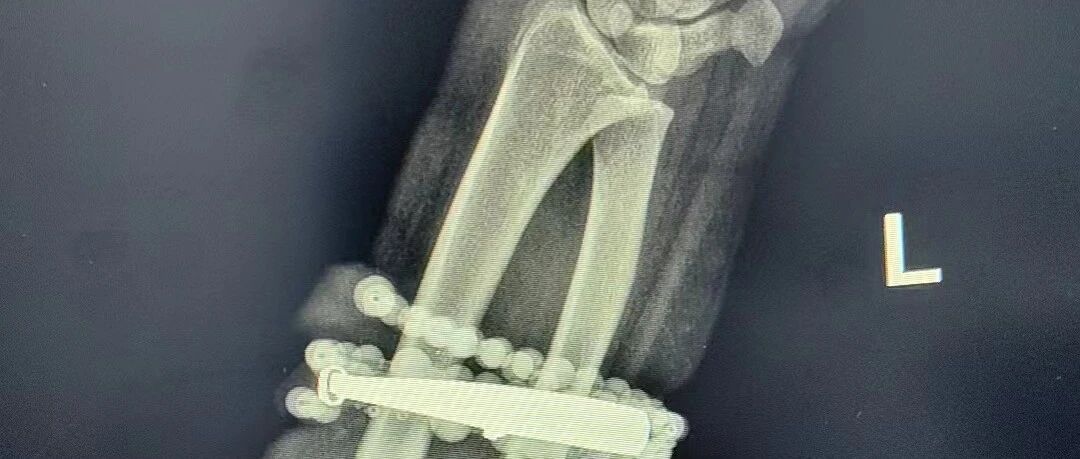

< 左右滑動查看更多 >

醫(yī)院迅速組建專業(yè)團(tuán)隊,制定手術(shù)方案。在經(jīng)過抗感染治療后,閩東醫(yī)院創(chuàng)傷骨科、手顯微外科張申申主任醫(yī)師主刀,為龔女士實施“前臂異物取出術(shù)+清創(chuàng)術(shù)”。

經(jīng)過一個多小時的精細(xì)操作,醫(yī)生們成功將手鐲和串珠從厚厚的增生組織中完整剝離出來。隨后,醫(yī)生對傷口進(jìn)行了徹底清創(chuàng)、沖洗,并放置引流條,確保感染不再復(fù)發(fā)。